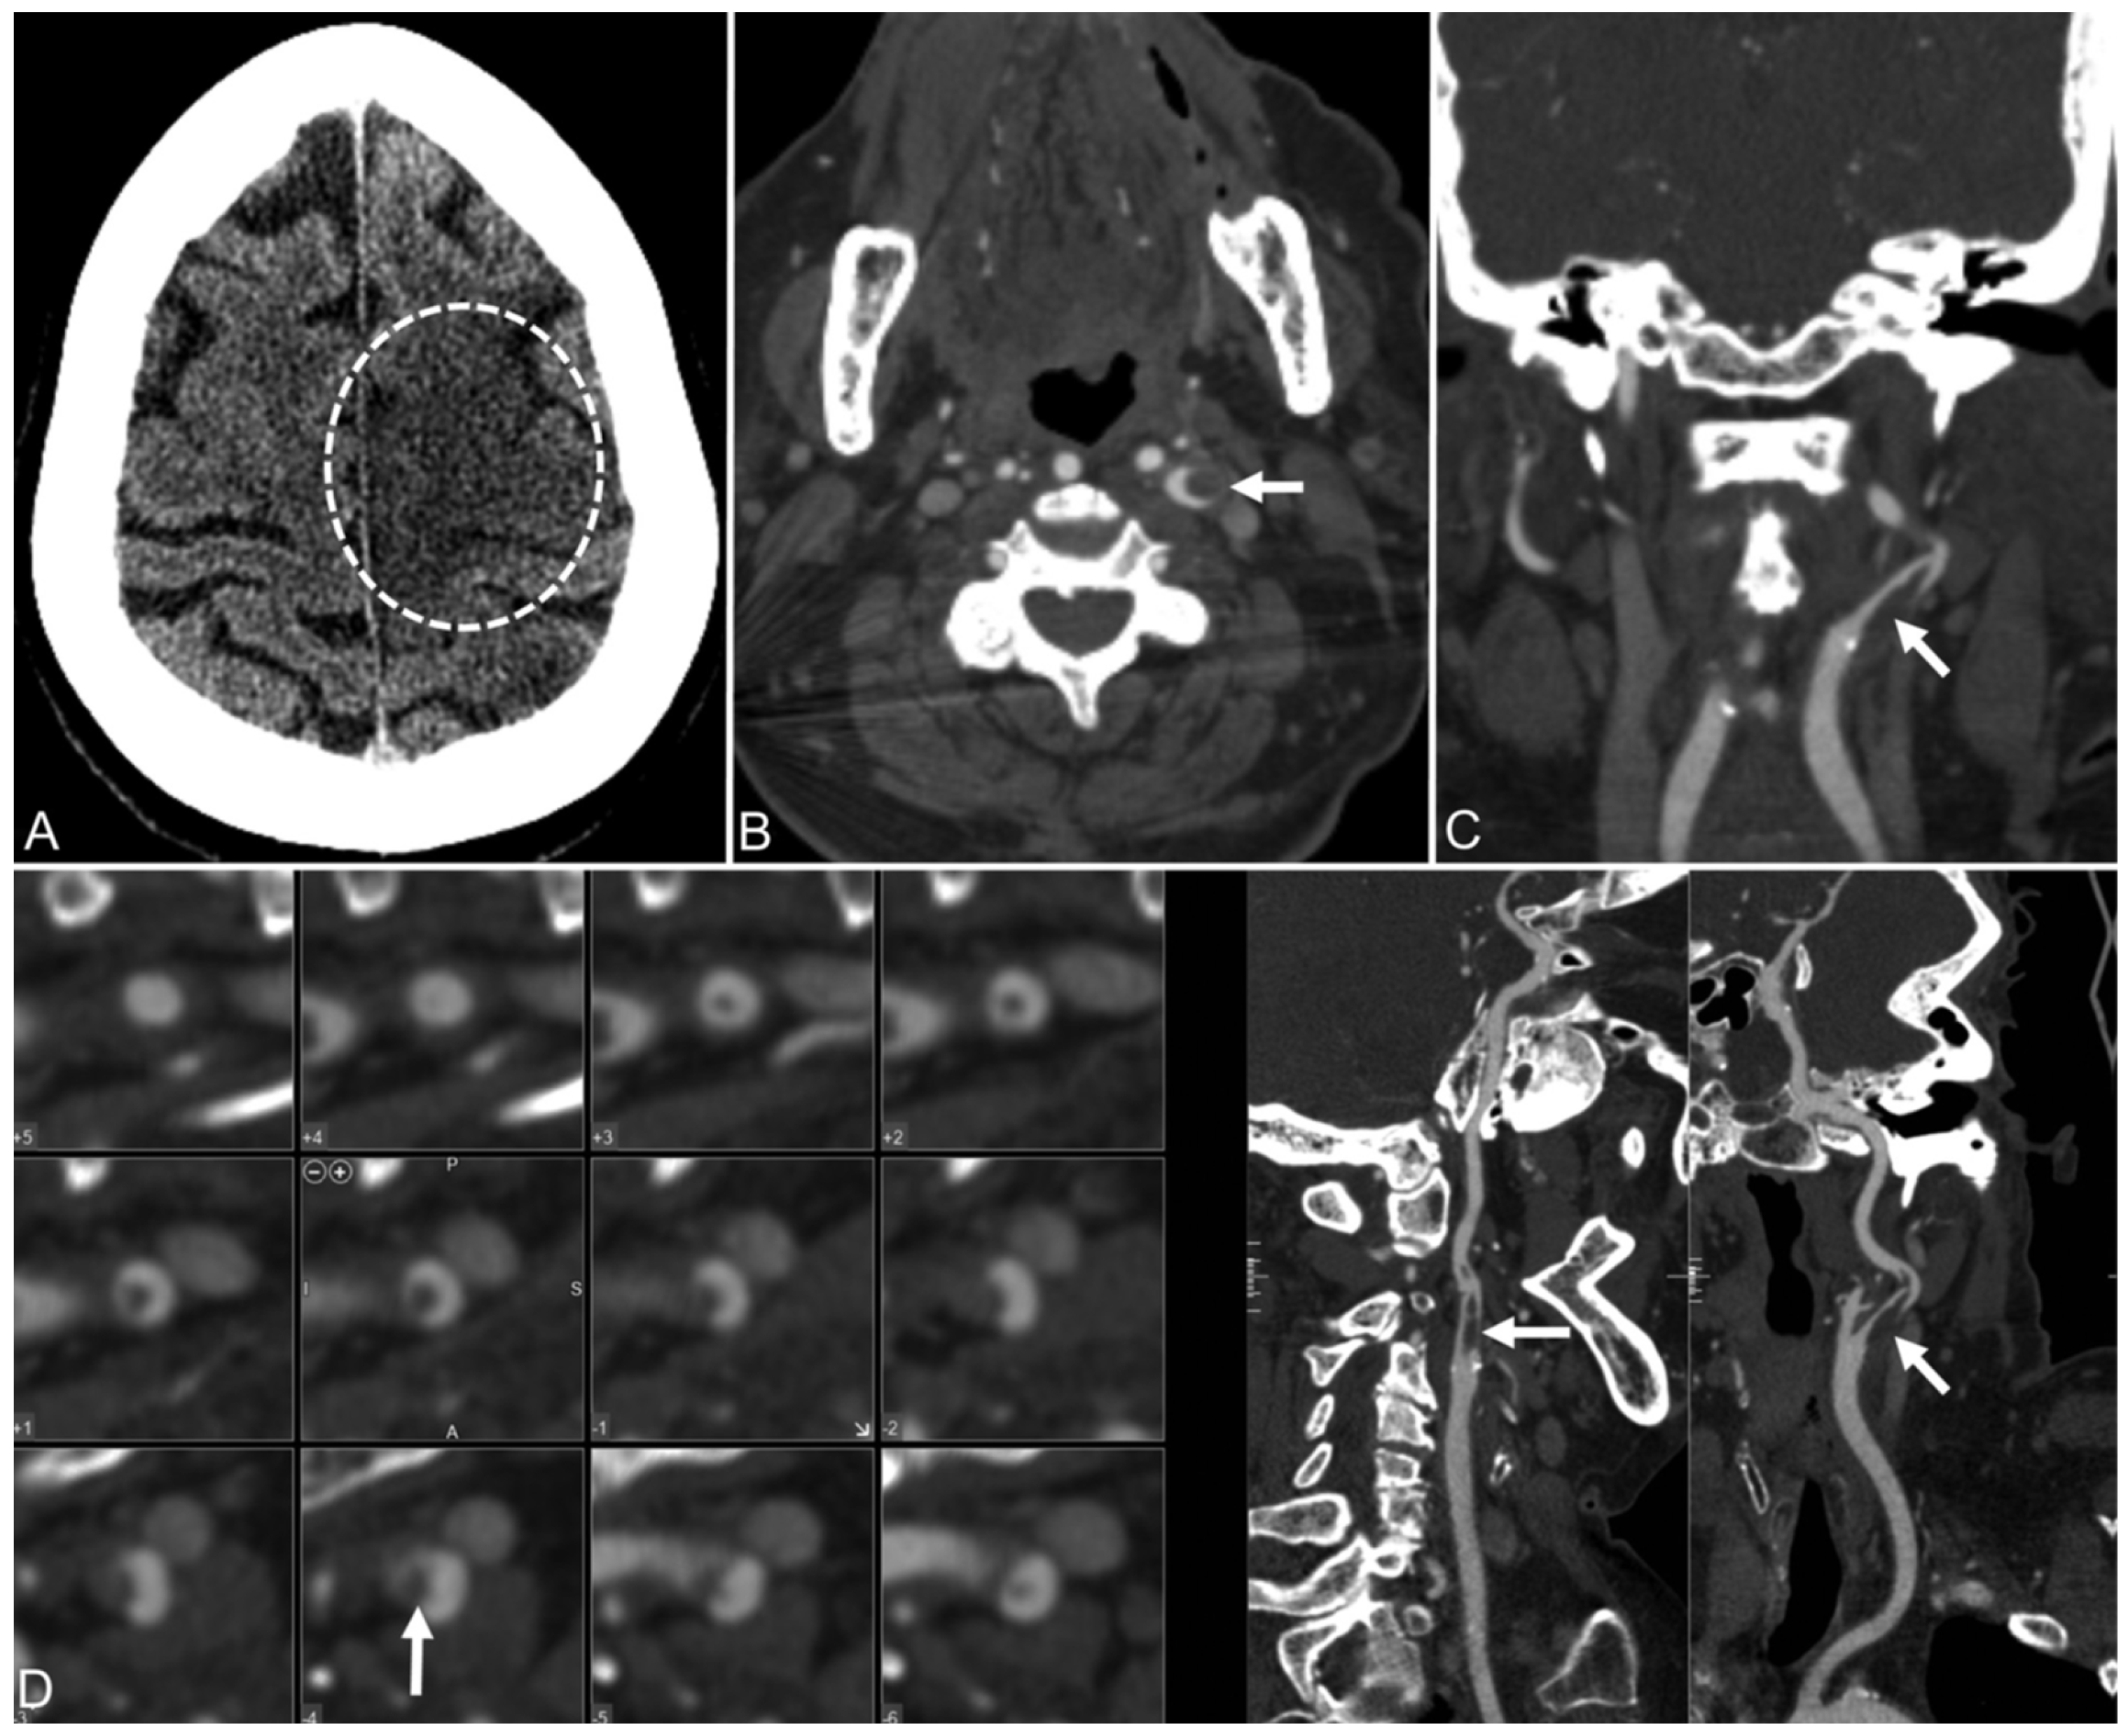

4.5. Coronary and Carotid Artery Images

- Mohamud, A.Y.; Griffith, B.; Rehman, M.; Miller, D.; Chebl, A.; Patel, S.C.; Howell, B.; Kole, M.; Marin, H. Intraluminal carotid artery thrombus in COVID-19: Another danger of cytokine storm? Am. J. Neuroradiol. 2020, 41, 1677–1682. [Google Scholar] [CrossRef]

- Alkhaibary, A.; Abbas, M.; Ahmed, M.E.; Khatri, I.A.; Alkhani, A. Common carotid artery occlusion in a young patient: Can large-vessel stroke be the initial clinical manifestation of coronavirus disease 2019? World Neurosurg. 2020, 144, 140–142. [Google Scholar] [CrossRef]

- Viguier, A.; Delamarre, L.; Duplantier, J.; Olivot, J.-M.; Bonneville, F. Acute ischemic stroke complicating common carotid artery thrombosis during a severe COVID-19 infection. J. Neuroradiol. 2020, 47, 393–394. [Google Scholar] [CrossRef]

- Doo, F.X.; Kassim, G.; Lefton, D.R.; Patterson, S.; Pham, H.; Belani, P. Rare presentations of COVID-19: PRES-like leukoencephalopathy and carotid thrombosis. Clin. Imaging 2021, 69, 94–101. [Google Scholar] [CrossRef]